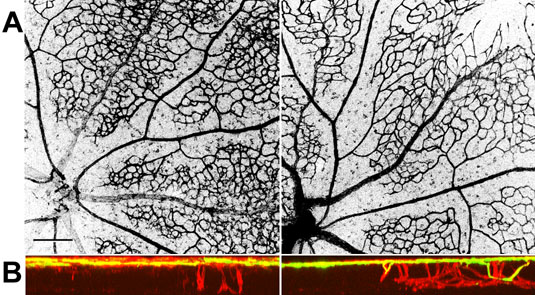

Figure 5. PEDF over-expression slows the rate of vessel differentiation and growth of vessels into the deeper layers of the retina

A: Extended focus confocal images of the structure of vascular trees in whole mount retinae from a P12 animal injected subretinally at P2. Vascular structures are visualized by immunohistochemistry with isolectin GS-IB4, which specifically labels endothelial cells. The retina injected with AAV2/1.CMV.PEDF (experimental eye) is shown on the left, and the fellow eye injected with AAV2/1.CMV.EGFP (control eye) is shown on the right. In both retinae, there is differentiation of vessels into arterioles (thinner vessels) and venules (thicker vessels). However, in the experimental eyes (left), the presumptive capillary structure retains a denser, more immature, polygonal vascular pattern compared to the control eyes (right). In the control eyes, there is a slightly sparser, more differentiated branching structure. B: The confocal cross-section reconstructions in the same retinae corresponding to those shown in the above in A. The yellow signal shows the distribution of fluorescein dextran after intracardiac injection, indicating the distribution of patent vessels in the vascular tree. The red signal shows the pattern of GS-IB4 labeling, indicating the structure of both patent vessels as well as nascent vessels that have not yet undergone cannulation. The experimental eyes (left) show a sparser distribution of nascent vessels in the deeper layers of the retina; many of these vessels have not yet undergone cannulation. However, in the control contralateral eyes, there is a greater number of vessels growing into the deeper layers with some vessels having already undergone cannulation.